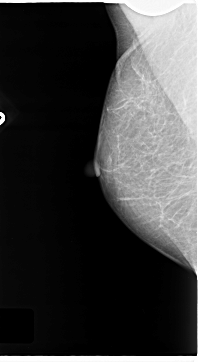

C_0122_1.RIGHT_CC

RIGHT_CC LINES 4688 PIXELS_PER_LINE 2336 BITS_PER_PIXEL 12 RESOLUTION 50 NON_OVERLAY